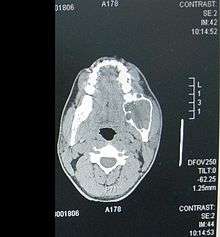

A CT scan of a patient suffering from an ameloblastoma.

Ameloblastomas are often associated with the presence of unerupted teeth. Symptoms include painless swelling, facial deformity if severe enough, pain if the swelling impinges on other structures, loose teeth, ulcers, and periodontal (gum) disease. Lesions will occur in the mandible and maxilla, although 75% occur in the ascending ramus area and will result in extensive and grotesque deformitites of the mandible and maxilla. In the maxilla it can extend into the maxillary sinus and floor of the nose. The lesion has a tendency to expand the bony cortices because slow growth rate of the lesion allows time for periosteum to develop thin shell of bone ahead of the expanding lesion. This shell of bone cracks when palpated and this phenomenon is referred to as "Egg Shell Cracking" or crepitus, an important diagnostic feature. Ameloblastoma is tentatively diagnosed through radiographic examination and must be confirmed by histological examination (e.g., biopsy). Radiographically, it appears as a lucency in the bone of varying size and features—sometimes it is a single, well-demarcated lesion whereas it often demonstrates as a multiloculated "soap bubble" appearance. Resorption of roots of involved teeth can be seen in some cases, but is not unique to ameloblastoma. The disease is most often found in the posterior body and angle of the mandible, but can occur anywhere in either the maxilla or mandible.